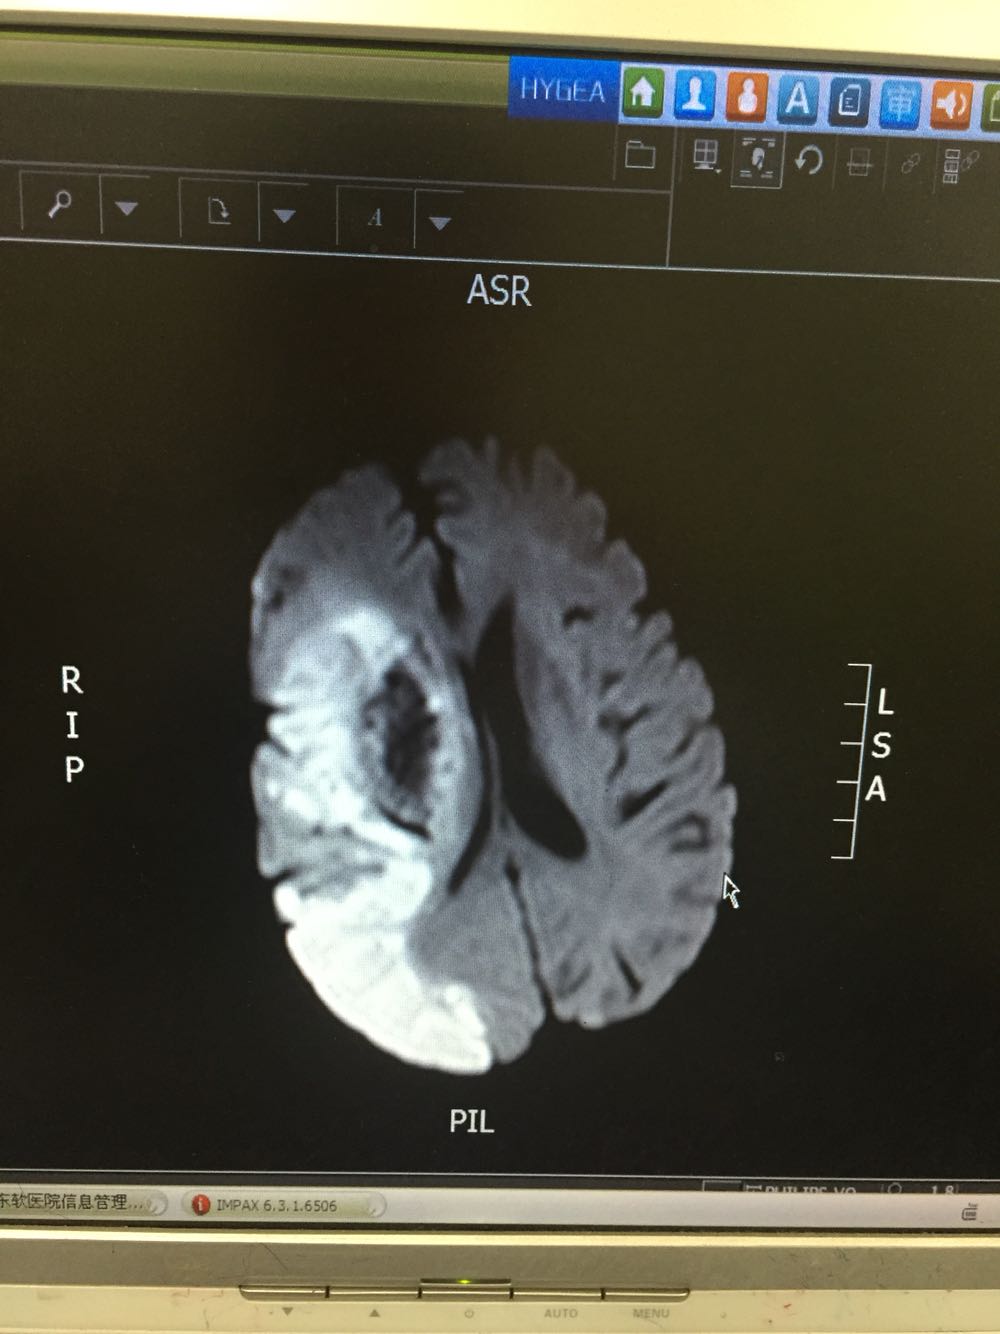

患者入院治疗后症状一度好转,左侧肢体肌力3级+,于入院后第二日病情突然加重,伴意识障碍,头DWI示:脑梗死伴脑出血 右侧大脑中动脉闭塞。停止当前治疗方案,脱水脑保护,营养神经对症治疗。入院后第5日复查头CT示:右侧大面积脑梗死,脑出血吸收期,伴左侧枕叶脑出血。患者左侧枕叶脑出血不好解释,能否是搬运及护理时外伤所致?